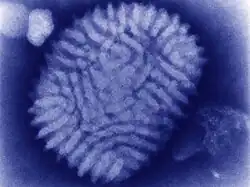

Myxoma virus is in the genus Leporipoxvirus (family Poxviridae; subfamily Chordopoxvirinae). Like other poxviruses, myxoma viruses are large DNA viruses with linear double-stranded DNA. Virus replication occurs in the cytoplasm of the cell. The natural hosts are tapeti (Sylvilagus brasiliensis) in South and Central America, and brush rabbits (Sylvilagus bachmani) in North America. The myxoma virus causes only a mild disease in these species, with symptoms limited to the formation of skin nodules.[1]

Diagnosis of myxomatosis in European rabbits is often made on the basis of the characteristic clinical appearance. If a rabbit dies without exhibiting the classic symptoms of myxomatosis, or if further confirmation is desired, a number of laboratory tests are available. Historically these have included histopathology, electron microscopy, and virus isolation. Histopathologic examination of affected skin typically shows undifferentiated mesenchymal cells within a matrix of mucin, inflammatory cells, and edema. Intracytoplasmic inclusions may be seen in the epidermis and in conjunctival epithelium.[6] Negative-stain electron microscopic examination can also used for diagnosis due to the large size and distinctive structure of poxviruses. This method allows rapid visualization of poxviruses, but does not allow specific verification of virus species or variants.[7] Virus isolation remains the “gold standard” against which other methods of virus detection are compared. Theoretically at least, a single viable virus present in a specimen can be grown in cultured cells, thus expanding it to produce enough material to permit further detailed characterization.[8]